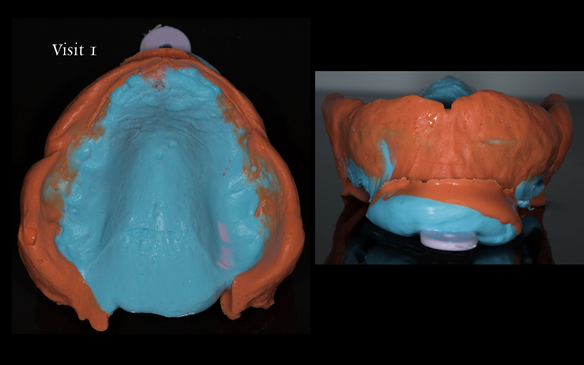

This newsletter describes in step by step detail the transition from acrylic based immediate dentures to metal based definitive dentures.

- Extraction of all upper teeth and LR5 and LL4 and fitting of immediate acrylic based (Mk 1) dentures - complete upper and lower partial

- Reviews of the immediate dentures and relines as needed over 9 - 12 months